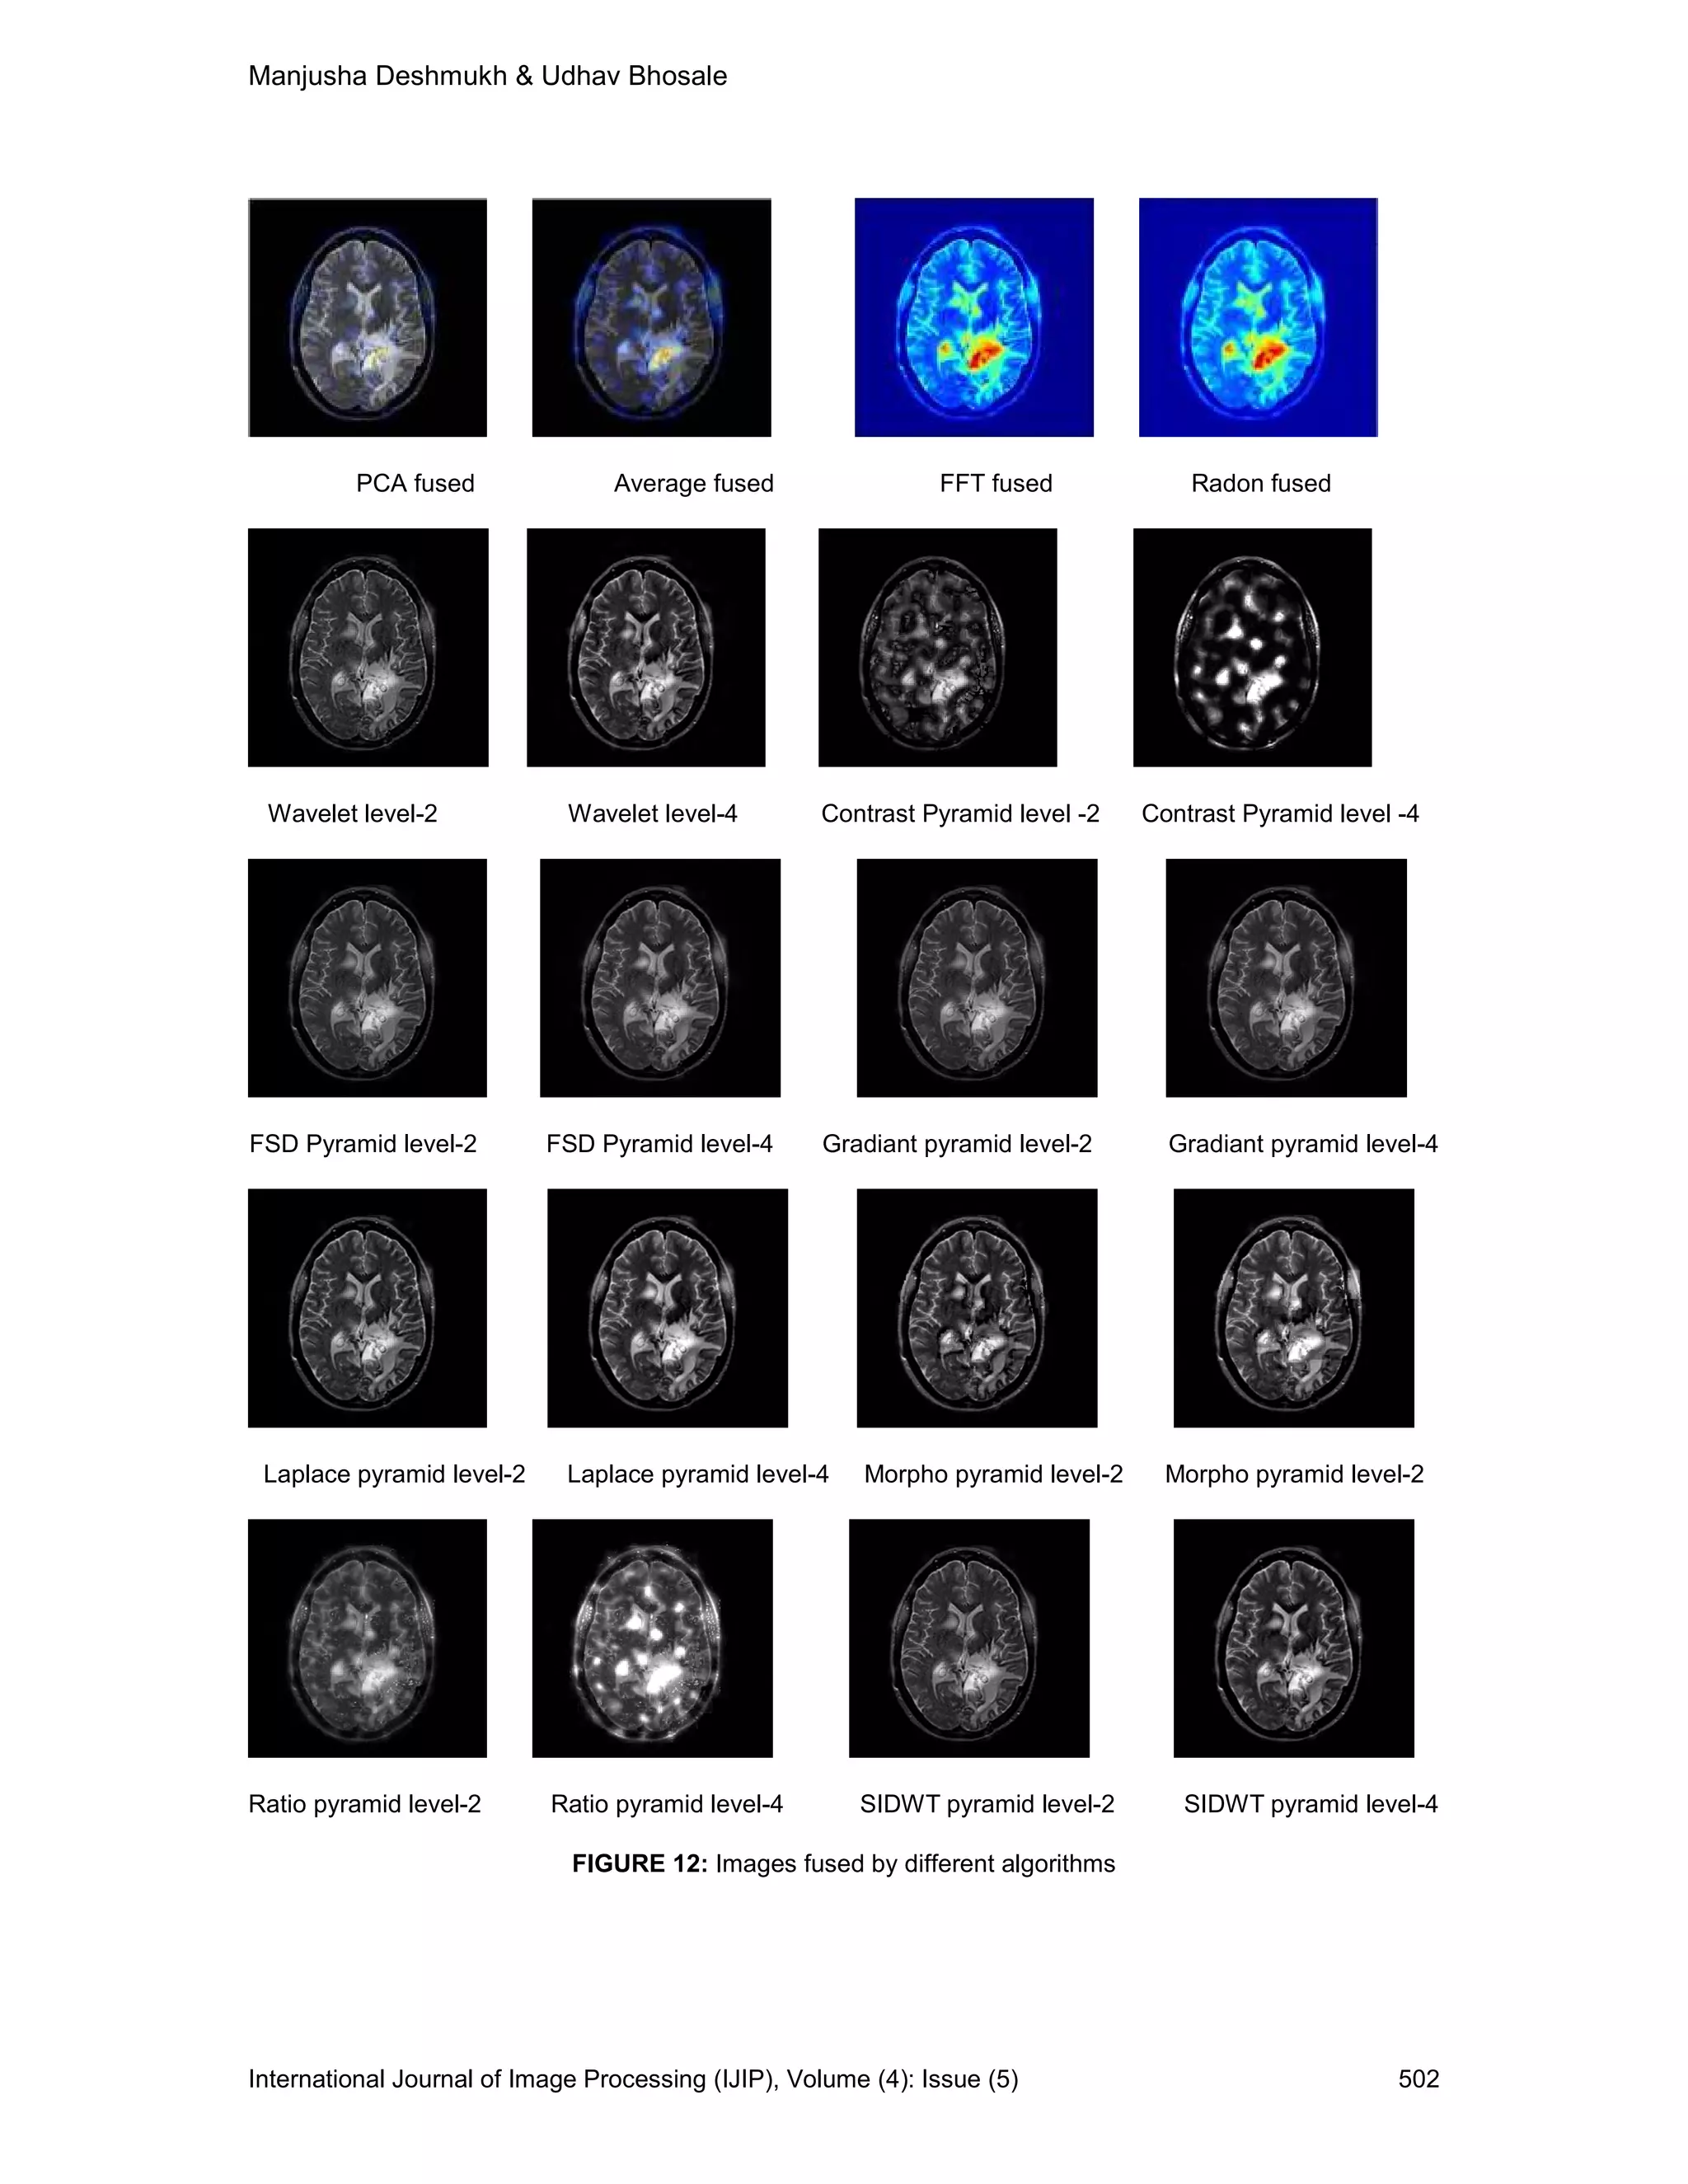

Data set 2 analysis

In this data set, SPECT image with tumor and MRI image of same tumor of size 256 x 256 are

considered for evaluation of the fusion algorithms. It can be seen that we get

Physiological/functional knowledge from Single Photon Emission Computed Tomography

(SPECT) while MRI gives anatomical information. Images are fused to have both types of

knowledge simultaneously. Table III gives the entropy of fused images and Table IV shows

Fusion Mutual Information.

PCA fused Average fused FFT fused Radon fused

Wavelet level-2 Wavelet level-4 Contrast Pyramid level -2 Contrast Pyramid level -4

FSD Pyramid level-2 FSD Pyramid level-4 Gradiant pyramid level-2 Gradiant pyramid level-4

Laplace pyramid level-2 Laplace pyramid level-4 Morpho pyramid level-2 Morpho pyramid level-2

Ratio pyramid level-2 Ratio pyramid level-4 SIDWT pyramid level-2 SIDWT pyramid level-4

FIGURE 12: Images fused by different algorithms

spatial resolution. Figure 12 shows fused images of MRI image and SPECT image of brain with

tumor. Brain tumor is clearly visible in SPECT image but not in MRI image . Figure shows that

although single-photon emission computerized tomography (SPECT) provides unique functional

information it is limited by poor anatomic detail. Non-specific localization of the antibody makes

image interpretation difficult, since contrast improvement offered by SPECT imaging increases

both the tumor specific and non-specific background uptake. Anatomy of brain can be observed

in MRI image , not in SPECT image, but fused image shows anatomy of brain as well as tumor.